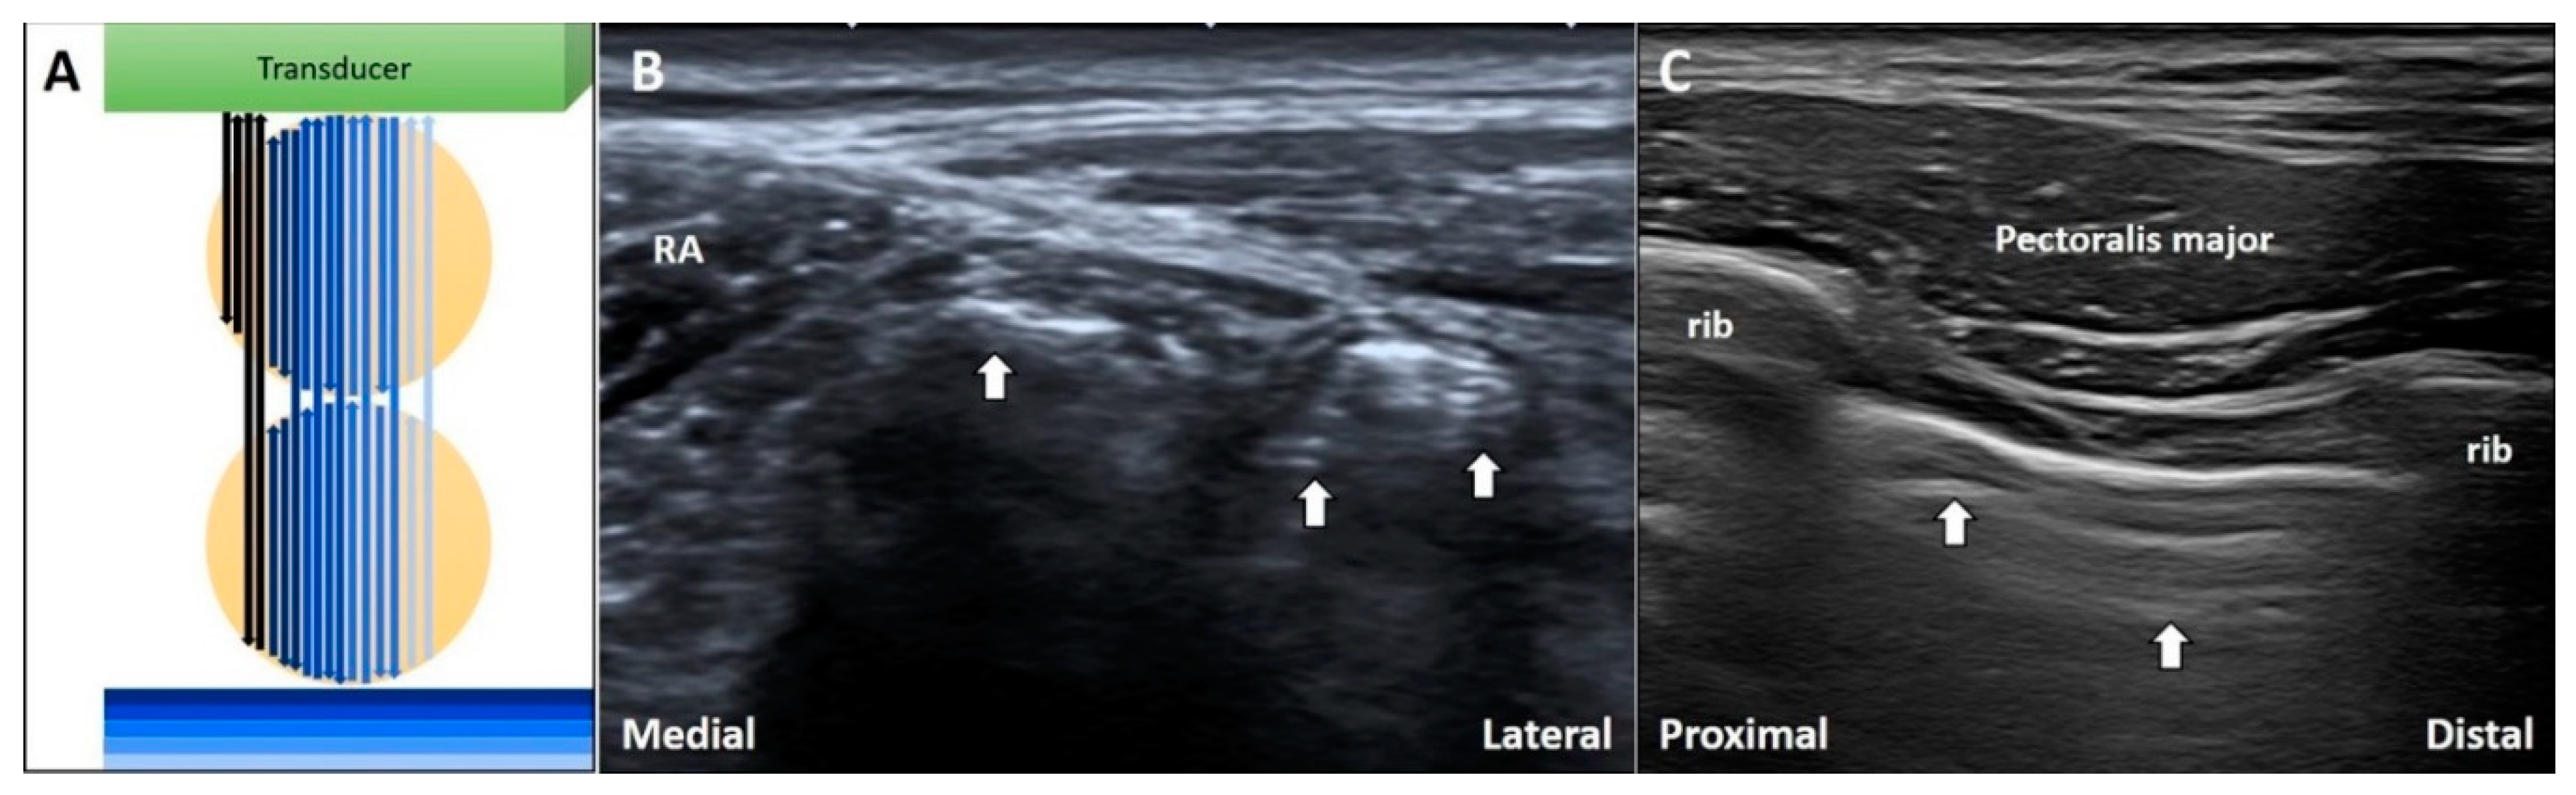

3.7. Side Lobe Artifact

3.7.1. Physics

3.7.2. Clinical Examples